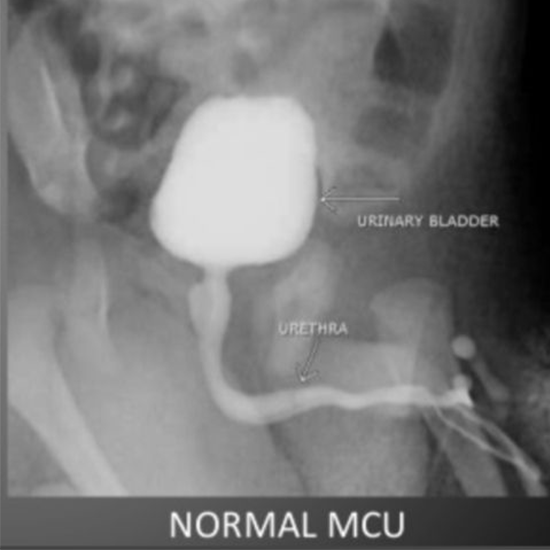

The micturating cystourethrogram (MCU), also known as the avoiding cystourethrogram, is a diagnostic imaging procedure used to examine the interior structures of the lower urinary tract.

What is the procedure for the Micturating Cystourethrogram (X-ray MCU) Radiograph Test?

X-Ray (MCU) Micturating Cysto-Urethrogram (Digital X-Ray